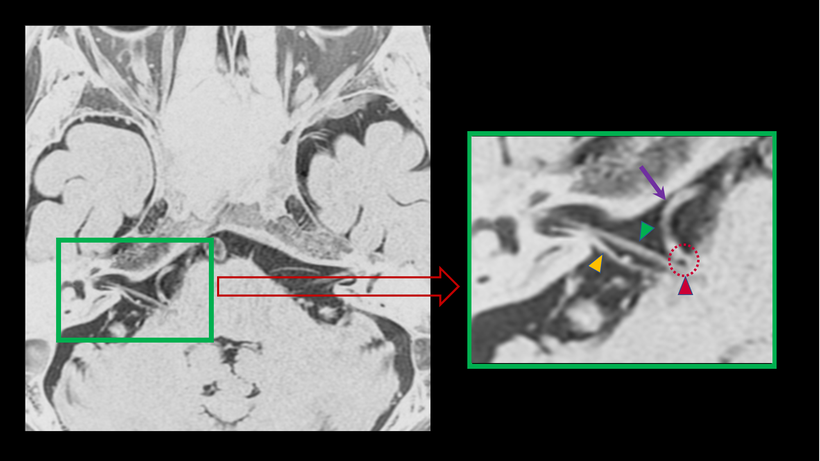

【 顔面痙攣の起きている事がわかるMRI画像-1 】

一般的に多く認められる画像所見です。聴神経(▲)の上を走行している顔面神経(▲)が認められます。蛇行した血管(動脈/↑)が、顔面神経の根元(▲)に当たっており圧迫している所見が認められます(点線○)。

【 顔面痙攣の起きている事がわかるMRI画像-3】

顔面神経の近くを走行していた太い血管(動脈:↑)が、次第に走行を変えて顔面神経の近くに寄っていく事が原因になります。この太い血管より枝分かれした血管(点線○)が、顔面神経の根元(▲)に当たっているのがわかります。この接触もしくは圧迫によって顔面の痙攣が発生します。顔面神経の下を走行しているのは、聴神経です。